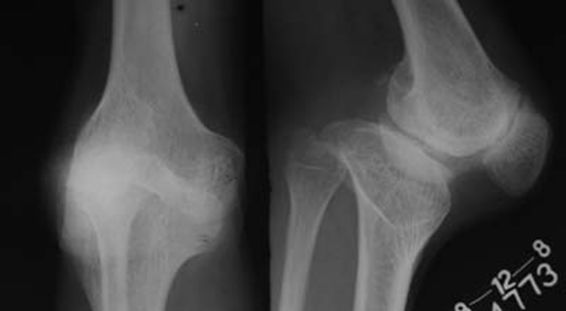

3、畸形:膝关节可出现内翻或外翻畸形,关节骨缘增大。有些患者不能完全伸直膝关节,严重者则膝关节呈屈曲挛缩畸形。

2、X线片(站立或负重位)示关节间隙变窄、软骨下骨硬化、和(或)囊性变、关节缘骨赘形成。

8、膝关节畸形改变,以膝关节内翻畸形最为常见。

1、关节间隙变窄:成人膝关节间隙为4mm,小于3mm即为关节间隙狭窄,60岁以上的老人膝关节间隙为3mm,小于2mm为关节间隙狭窄。

2、软骨下骨板硬化:软骨下骨板致密、硬化,负重软骨下骨质内可见囊性改变。

3、骨赘形成。